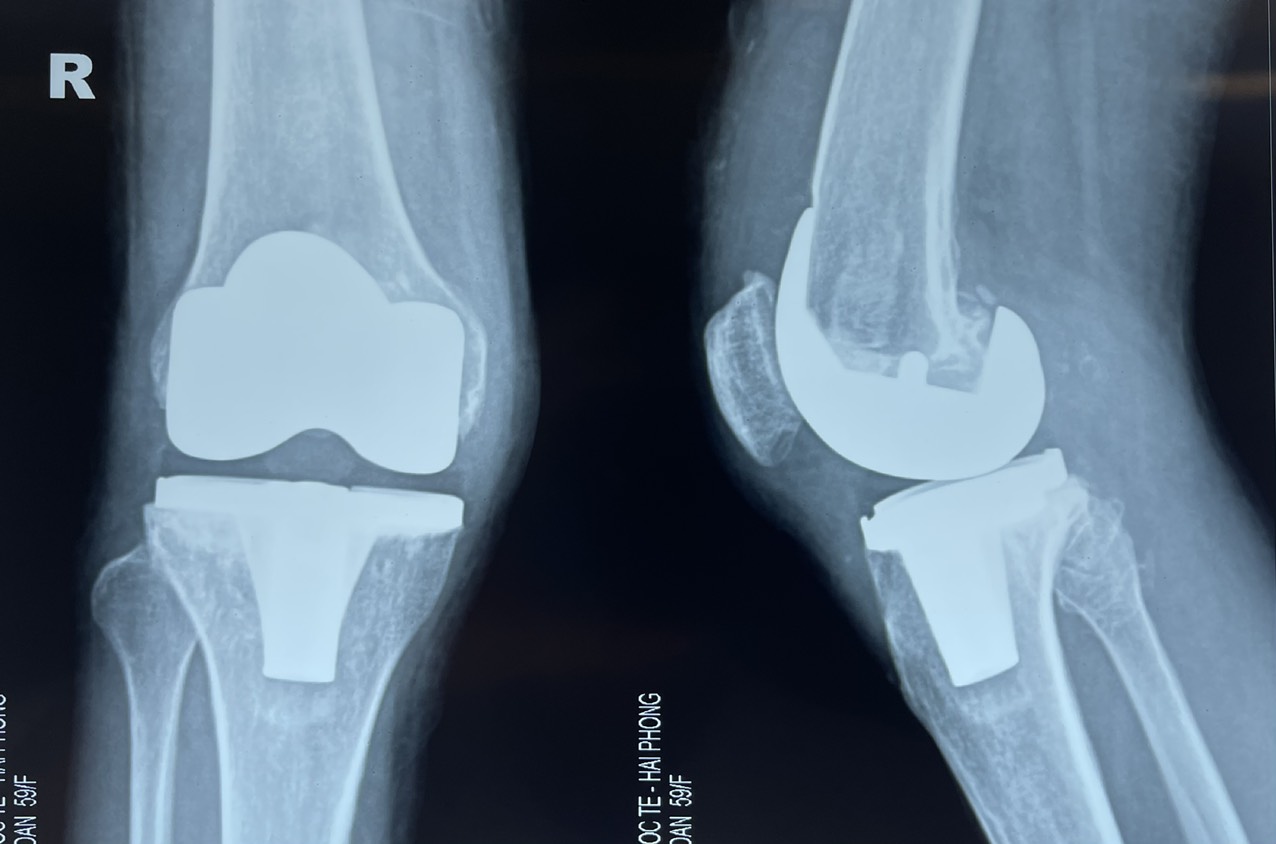

- Hình ảnh Xquang sau mổ của bệnh nhân: khớp gối phải nhân tạo thẳng trục

Ca mổ diễn ra trong 90 phút và thực hiện rất thành công. Sau phẫu thuật, tình trạng sức khỏe bệnh nhân ổn định, biến dạng chân đã được khắc phục hoàn toàn. Sau 5 ngày sau mổ, bệnh nhân đã tập đi lại nhẹ nhàng với chương trình phục hồi chức năng sau mổ chuẩn kết hợp phương pháp giảm đau đa mô thức cho bệnh nhân thay khớp. Đến ngày thứ 10 sau mổ bệnh nhân đã co duỗi được gối mổ nhẹ nhàng, duỗi hết tầm và gấp được khoảng 110 độ, vết mổ liền tốt, gối mổ không sưng đau, bệnh nhân cảm thấy thật hạnh phúc với sự hồi phục chức năng gối mổ nhanh như vậy.